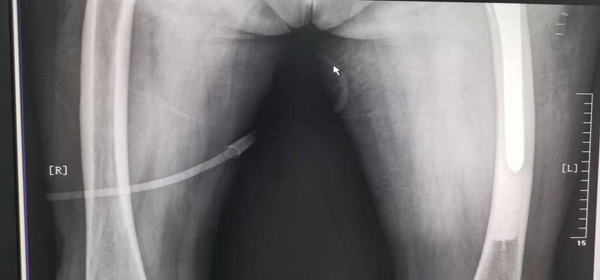

术后X线片